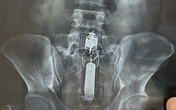

GiadinhNet - Các bác sĩ Bệnh viện 175 đã tiến hành phẫu thuật lấy bỏ khoảng 1kg dị vật kim loại dã bị ăn mòn một phần như đinh, thìa, bấm móng nay, lưỡi dao, thỏi sắt, móc đồ... trong bụng bệnh nhân.

Tags: bệnh viện 175, người nuốt đinh, Bệnh viện Quân y 175, Hội chứng Pica, dấu hiệu trầm cảm, người ăn đinh